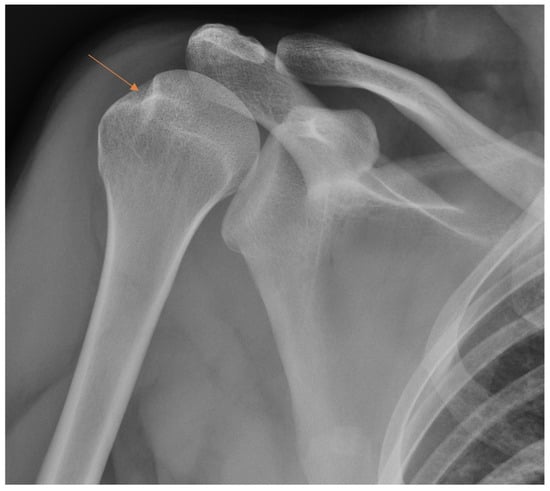

Patient with anterior shoulder dislocation. The radiology specialist missed a Hill–Sachs lesion (arrow) that resulted in delay in patient treatment.

Figure 6.